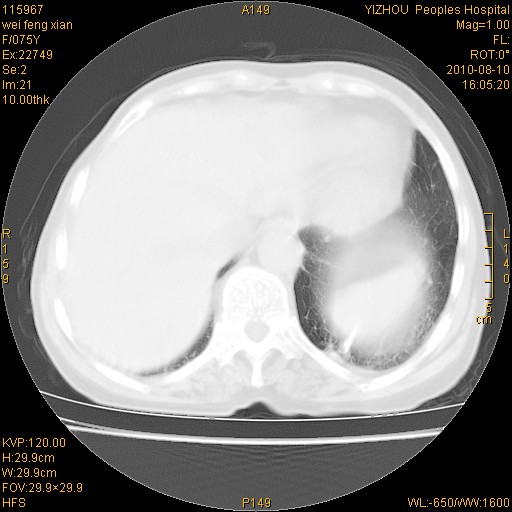

标题: CT28313:两肺弥漫性病变 [打印本页]

标题: CT28313:两肺弥漫性病变

女,75岁,患者反复头昏乏力面色苍白3年,再发10天入院。临床贫血查因。

双肺间质增生并右肺上叶炎性改变,不除外右肺上叶结核病肺内播散

考虑右肺上叶炎症合并双肺结核可能性大,建议上传纵隔窗ct图片。

双肺结核可能性大

考虑尘肺并结核;右上肺支气管扩张!

结核、尘肺、支气管肺泡癌都不能除外

右肺上叶继发性肺结核伴肺内血型播散!

考虑右肺上叶继发性肺结核伴两肺播散。